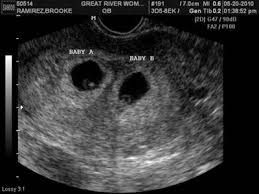

Through vaginal ultrasound the sound waves are very likely produce a clearer image at this stage. An ultrasound scan at 6 weeks is a must for any pregnant woman not just to evaluate the health of the child but that of the mother too. At 6 weeks an abdominal ultrasound is not likely to produce a very clear photo and your doctor will likely perform a vaginal ultrasound to get a look at the growing embryo. If you re having your first pregnancy ultrasound at 6 weeks there are some things you should be aware of.

The heartbeat is already there and is audible if you get an ultrasound. Vaginal ultrasounds are performed using a wand shaped vaginal ultrasound machine that is inserted into the vagina to produce an image. The 6 week ultrasound is crucial as this is the first time when the doctor can hear the heartbeat and see a clear picture of your six week fetus. It also helps decrease anxiety and helps take necessary and prompt actions in case of abnormalities.